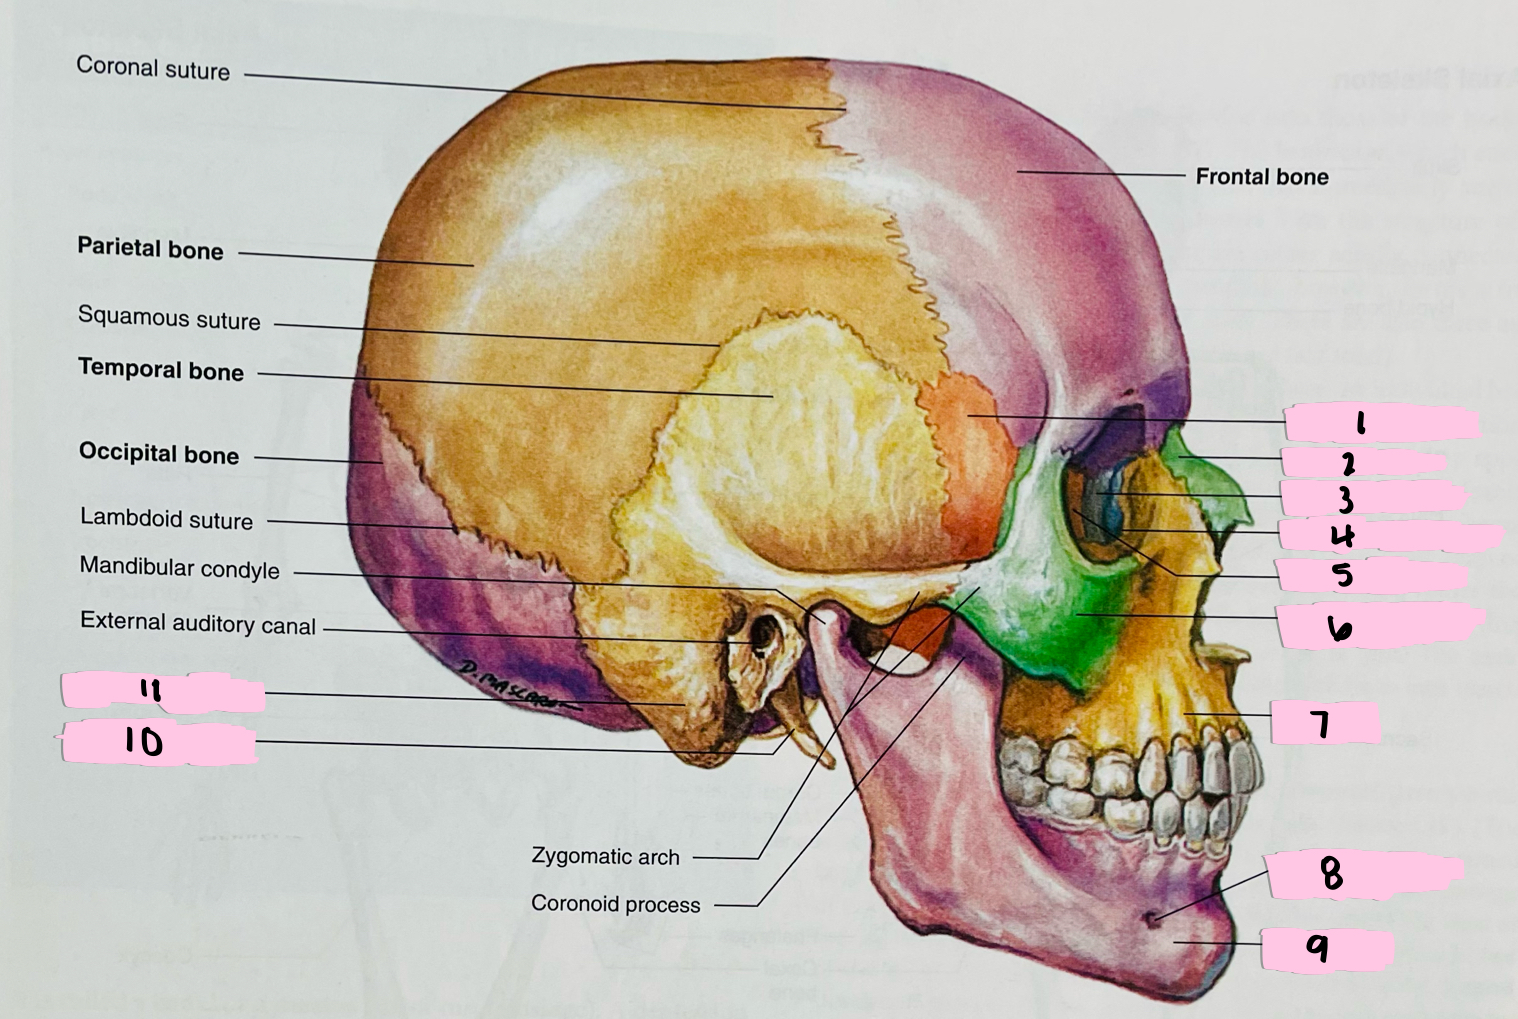

What is 1 pointing to?

Sphenoid bone

What is 2 pointing to?

Nasal bone

What is 3 pointing to?

Lacrimal bone

What is 4 pointing to?

Nasolacrimal canal

What is 5 pointing to?

Ethmoid bone

What is 6 pointing to?

Zygomatic bone

What is 7 pointing to?

Maxilla

What is 8 pointing to?

Mental foramen

What is 9 pointing to?

Mandible

What is 10 pointing to?

Styloid process

What is 11 pointing to?

Mastoid process